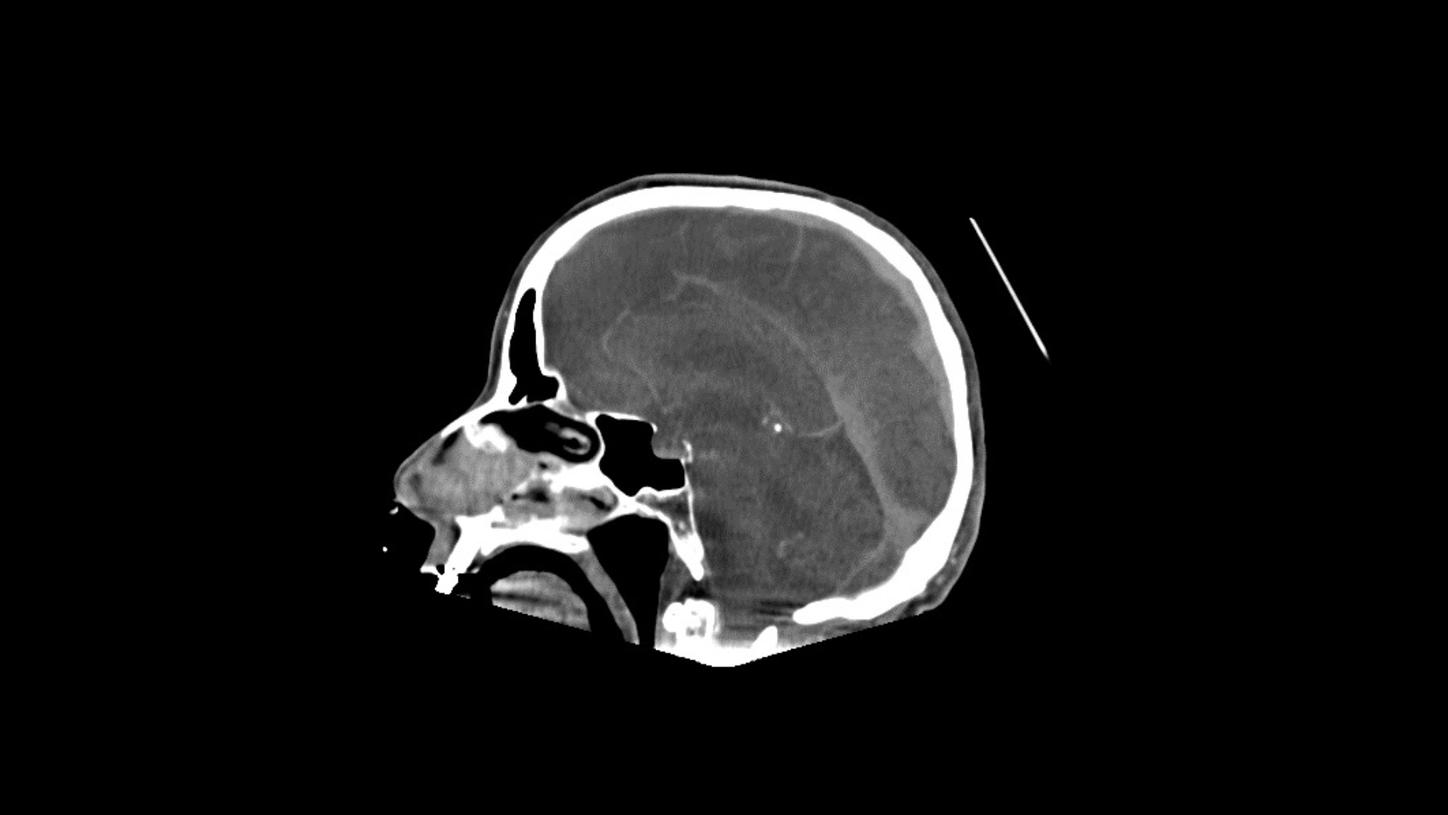

Native head scan

Assist with or support differential diagnosis of acute stroke with excellent gray-white matter differentiation and contrast enhancement